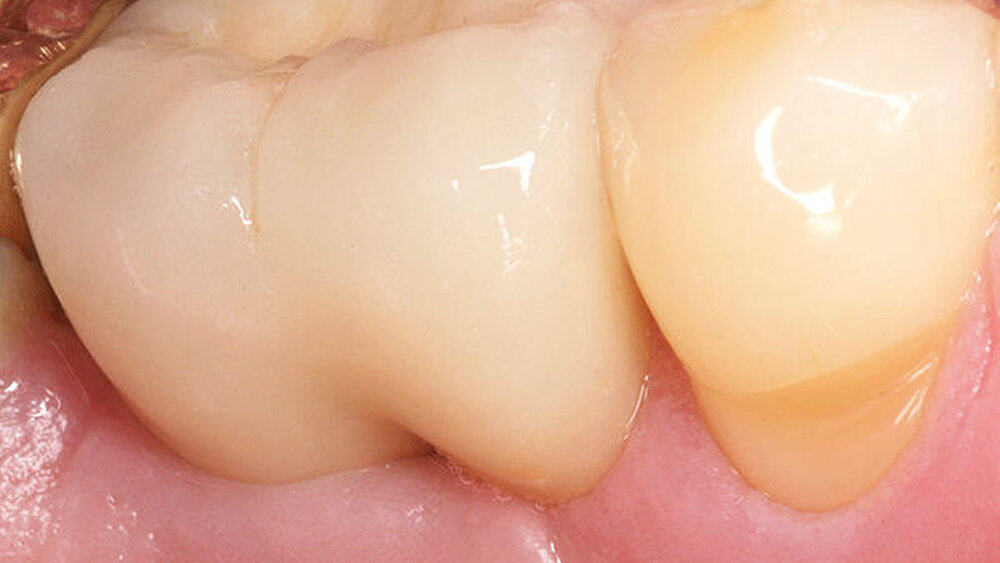

Weil man mit vorgefertigten Teilen arbeitet und die Darstellung der Präparationsgrenze entfällt. Der Scanner erkennt, was man scannt, auch unter dem Zahnfleisch, denn das Implantat ist in der Software hinterlegt. Bei einteiligen Implantaten spielt der optische Abdruck seine Stärken noch besser aus. Auf dem virtuellen Modell lässt sich das Zahnfleisch etwas radieren, um eine minimal subgingivale Lage des Randes der Präparation zu erreichen. Zudem braucht es keinen Scanbody, es sei denn, man beschleift das Implantat und verändert seine Originalform.

Zusätzlich kann das Emergenzprofil bereits intraoperativ in der Implantationssitzung gesteuert werden. Der Scan der ausgeheilten Situation vor der prothetischen Versorgung eröffnet die Möglichkeit, durch Einmatchen des Implantats in den Datensatz die subgingivale Situation zu simulieren ohne die Darstellung einer „Präparationsgrenze“ durch das Einlegen von Fäden. Diese Manipulationen sind traumatisch und zerstören die sensible hemidesmosomale Anhaftung der Gingiva- und Bindegewebsfasern an der Implantatoberfläche. Der digitale Abdruck wird die konventionelle Abformung in der modernen Zahnarztpraxis aufgrund seiner überlegenen Performance ersetzen. Den parodontologischen und minimalinvasiven Prinzipien folgend, ist die digitale Abformung von Zähnen auch in der ästhetisch sensiblen Zone angesichts der geringeren Traumatisierung der parodontalen Gewebe, der überragenden Präzision und der daraus folgenden Randpassung der Versorgung ein logischer und richtiger Weg in die Zukunft der zahnärztlichen Praxis (Abb. 10 – 14).